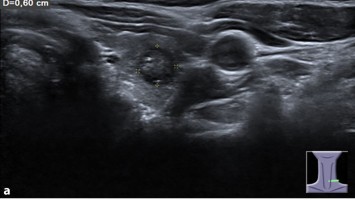

Update Medulläres Schilddrüsenkarzinom – Was ist für die Chirurgie relevant?

Kutane Arzneimittelreaktion/© Hötzenecker, W., Heimlich-Manöver/© Widmer, N; Heimes, D / all rights reserved Springer Medizin Verlag GmbH, Aufbau bei einer endoskopische Mittelohrchirurgie/© Mir-Salim P., Berlin, Wespen auf Stein/© merlion / Getty Images / iStock (Symbolbild), Schilddrüse einer Patientin wird untersucht/© Werner / stock.adobe.com (Symbolbild mit Fotmodellen), Volumetrie des Bulbus olfactorius/© Keweloh S.. et al. doi.org/10.1007/s00106-025-01650-z unter CC-BY 4.0, Augen und Nase einer Frau/© AlexanderFord / Getty Images / iStock (Symbolbild mit Fotomodell), Eine ältere Frau schaut in die Ferne/© RgStudio / Getty Images / iStock (Symbolbild mit Fotomodell), Transnasales Ösophagoskop/© F. Michel, Seeheim-Jugenheim, Ex vivo konfokales Laserscanmikroskopiebild eines Morbus Bowen/© Grunewald S et al. / all rights reserved Springer Medizin Verlag GmbH, Einweckglas mit Hering/© FoodieMedia / Getty Images / iStock (Symbolbild), Zwei Injektionspens mit Semaglutid/© Kassandra / Stock.adobe.com, Gewitter mit Blitzschlag/© solarseven / Getty images / iStock, Ulzerative Form des oralen Lichen planus/© Abdusalamov K. et al. doi.org/10.1007/s00105-025-05540-x unter CC-BY 4.0, Otitis externa/© Dr. P. Marazzi / Science Photo Library (Symbolbild), VMAT-Bestrahlungsplan einer definitiven Radiochemotherapie eines linksseitigen, lokal fortgeschrittenen Tonsillenkarzinoms/© Schnellhardt, S et al. / all rights reserved Springer Medizin Verlag GmbH, Frau hustet/© Suzi Media Production / Getty Images / iStock (Symbolbild mit Fotomodell), Tympanometrie bei einer Frau/© Viacheslav Yakobchuk (Symbolbild mit Fotomodell), Stimmlippeninjektion in der HNO-Praxis/© Markus Hess, Mann erhält eine Spritze im Gesicht/© Alvaro / Stock.adobe.com (Symbolbild mit Fotomodell), Ein Arzt sprüht ein antimikrobielles und entzündungshemmendes Spray in den entzündeten Hals eines Mädchens./© HENADZY / Stock.adobe.com (Symbolbild mit Fotomodell), Junger Mensch bekommt Spritze verabreicht/© mapo / Getty Images / iStock (Symbolbild mit Fotomodellen), Bestrahlungsplans einer Wirbelsäulenmetastase eines oligometastasierten Prostatakarzinoms/© Springer Medizin Verlag GmbH, Cholesterolgranulom im MRT/© Frederik F/ all rights reserved Springer Medizin Verlag GmbH, Schimmelbefall an der Wand/© Bigy / Stock.adobe.com (Symbolbild), Rasterelektronenmikroskopische Aufnahme von Nanopartikeln/© Hansen S. et al. doi.org/10.1007/s00106-025-01633-0 unter CC-BY 4.0, Medulläres Schilddrüsenkarzinom linker Schilddrüsenlappen in der Sonographie/© Lorenz K et al. / all rights reserved Springer Medizin Verlag GmbH, Sonnenhüte (Echinacea)/© Wieland Teixeira / Getty Images / iStock (Symbolbild mit Fotomodell), Körperstereotaxie einer Lebermetastase im Segment VIII am MR-LINAC/© Ehret, F. et al. / all rights reserved Springer Medizin Verlag GmbH, Eine ältere Frau riecht an einem Basilikumblatt/© Halfpoint / Stock.adobe.com (Symbolbild mit Fotomodell), Mann hustet/© kostyha / stock.adobe.com (Symbolbild mit Fotomodell), Titel/© J. Hornung, Erlangen, Senior hält sich vor Schmerzen an den Hals/© brizmaker / Getty Images / iStock (Symbolbild mit Fotomodell), Chor von älteren Menschen/© Highwaystarz-Photography / Getty (Symbolbild mit Fotomodellen), Eine junge Frau spült sich mir einer Nasenspülung die Nase/© puhhha / Getty Images / iStock (Symbolbild mit Fotomodell), Kleiner Junge mit Pille auf der Zunge/© redpepper82 / stock.adobe.com (Symbolbild mit Fotomodell), Frau mit Kopfschmerzen/© MaximFesenko / Getty Images / iStock (Symbolbild mit Fotomodell), Normaler Verlauf nach Hirntumor?/© Wolfgang Freund, Szintigraphie der Schilddrüse mit zwei Knoten/© AniphaeS / Getty Images / iStock, Patient mit Bauchschmerzen beim Arzt/© anon / Stock.adobe.com (Ausschnitt; Symbolbild mit Fotomodellen), Mann erleidet Schwindel/© Tunatura / Getty Images / iStock (Symbolbild mit Fotomodell), Ärztin untersucht ältere Frau/© peopleimages.com / stock.adobe.com (Symbolbild mit Fotomodellen), Infusion/© georgeoprea9 / Getty Images / iStock, Frau wird Blut abgenommen/© andresr / Getty Images / iStock (Symbolbild mit Fotomodellen), Junge Ärztin vor einem Triage-Zelt/© Milos / Stock.adobe.com (Symbolbild mit Fotomodell)